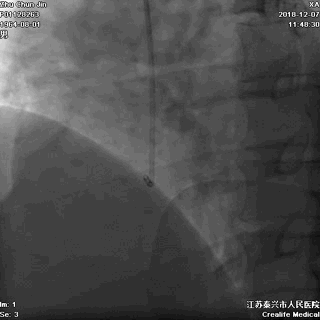

▲左冠无严重狭窄

▲右冠不好找呀!

▲非选择性右冠造影,血管通着咧!

▲在主动脉根部推造影剂,似乎也看不出太多异常

难道胸痛的原因 是冠状动脉痉挛?

胸部透视,看看心影吧:

▲胸部透视见纵隔影似乎明显增宽!是夹层吗?